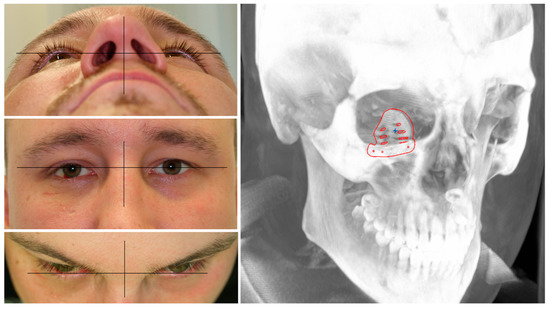

For visualization, we used the Magic Leap Device, driven by the Brainlab Elements software package. This mixed reality device can project 3D objects via semi-transparent glasses into the field of view of the carrier and allow interaction via a motion-sensing pointer device. The projected object can be freely inspected by the viewer by either moving it in three-dimensional space with the help of the pointer device or by freely moving around the projection via locomotion. By stepping through the object, a cut-through plane is automatically generated, which allows an intersection view in different planes depending on the viewing angle of the object. Thereby, an immersive inspection of the planning data displaying the different modes of reconstruction of the patient’s individual anatomy and fracture type by the patient himself was possible. The demonstration of the data sets revealed a mismatch of the pre-fabricated titanium mesh with a distance of 1.5 mm to the mirrored floor and a gap of 1.5 mm to the posterior ledge. Compared to the PSI, which adapts perfectly to the reconstructed anatomical shape as it was designed that way, the usage of the pre-fabricated titanium mesh would pose the need for intra-operative adaptation to the patient’s anatomy, as further pointed out by the virtual comparison (see Figure 3).

Figure 3.

Demonstration of the data set to the patient via mixed reality device Magic Leap. A mismatch with distances of the pre-fabricated titanium mesh to the orbital floor of 1.4 mm and a gap of 1.5 mm to the posterior ledge reveal the need for intra-operative adaptation for a perfect fit compared to the PSI.

The whole data set was also presented to the patient via the MR device. The demonstration of the fracture pattern, defect size, and different modes of reconstruction greatly enhanced the patient’s education. As it was decided to use a PSI, arguments for this surgical decision could be visualized for the patient, enhancing their understanding and leading to greater compliance. The advantages of an easier, more achievable, and more predictable reconstruction result as demonstrated via MR could be countered by the disadvantages of delayed surgery and higher costs, which have been made fully transparent to the patient.